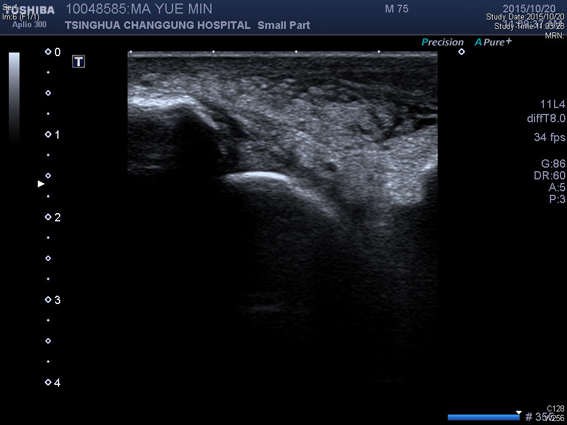

踝关节超声提示:右踝关节边缘可见少量骨质增生,外侧可见局部软组织水肿增厚。

超声引导右侧踝关节腔内PRP注射